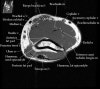

2. Axial section

1) The tendons of the Biceps Brachii and Brachiallis muscles transversely as they insert onto the Radius and Ulna respectively. 2) The distal Triceps tendon is also well evlauated in this plane.